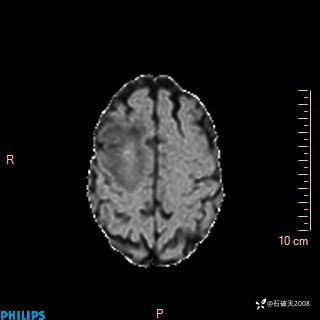

2020.11.14MR

T2

T1

FLAIR

DWI

ADC

增强轴位

增强矢状位

增强冠状位